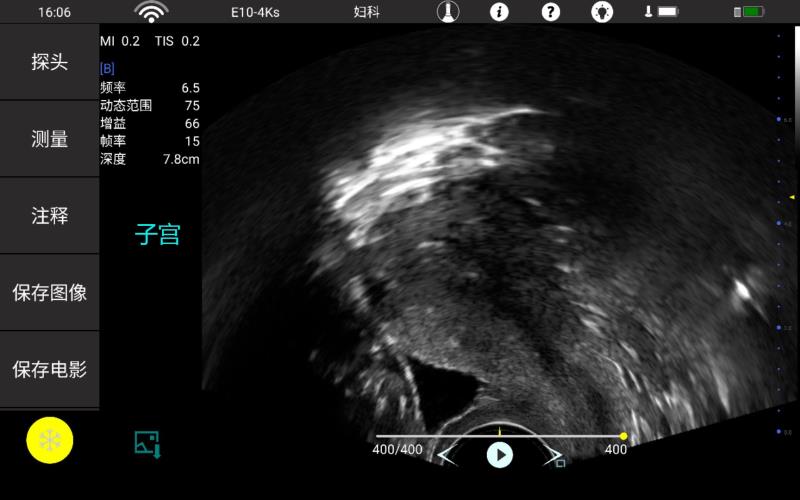

• 腔内

妇产科

泌尿科